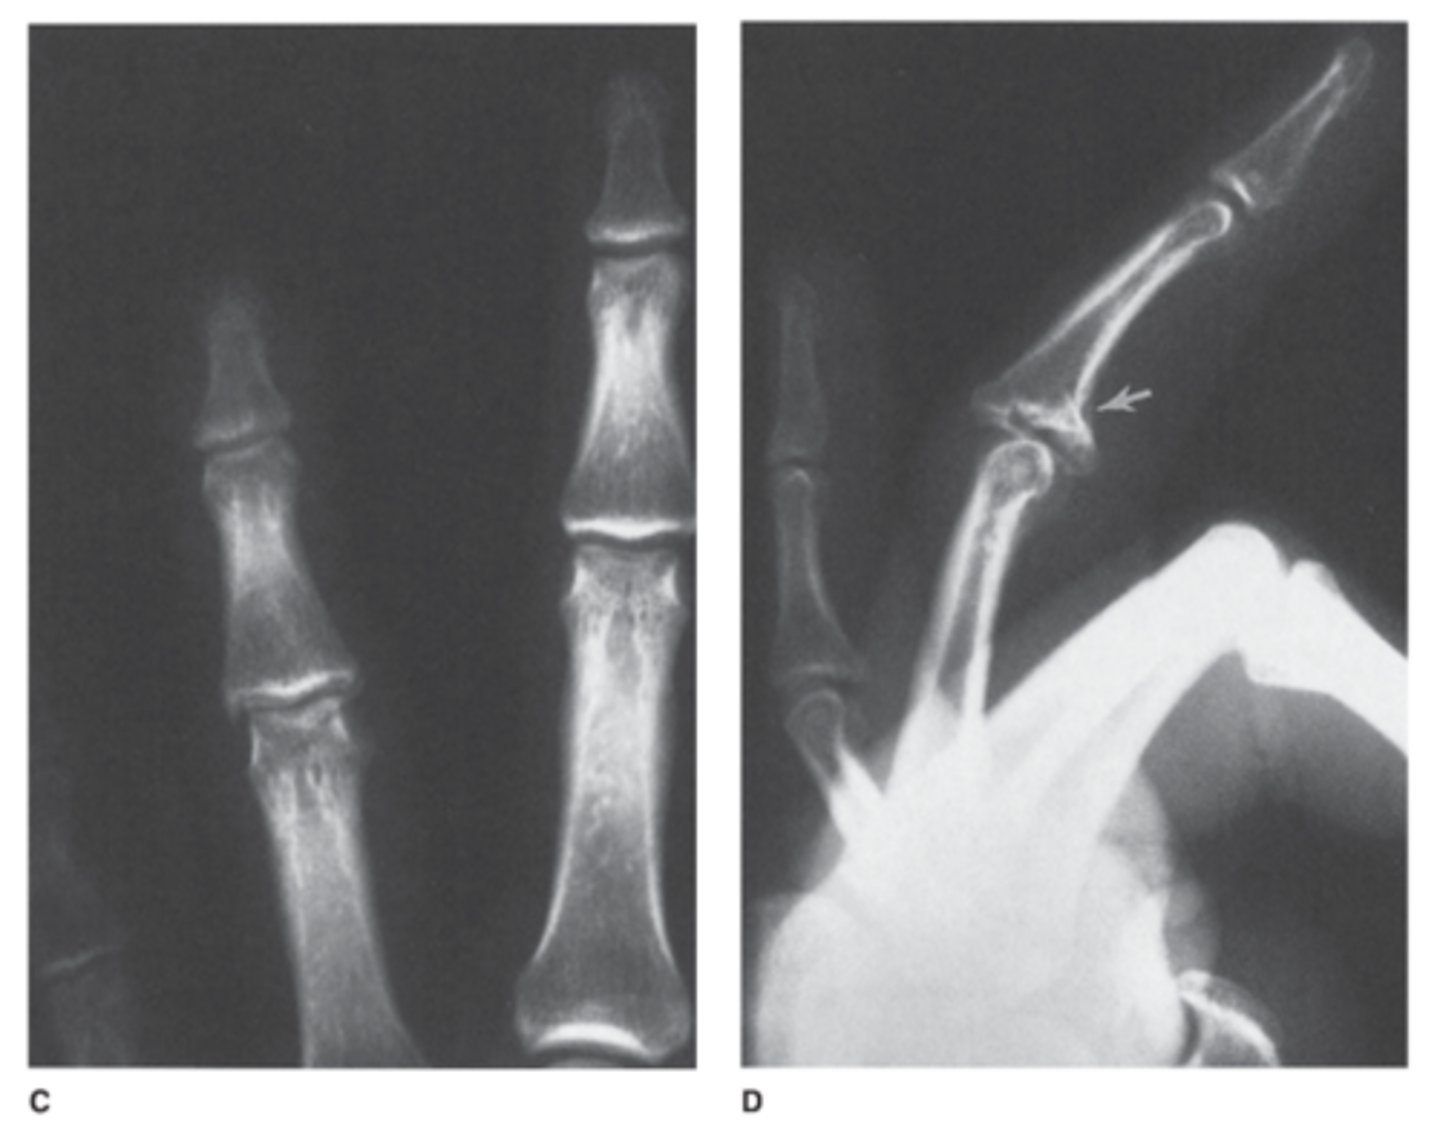

What are the signs of child abuse seen here?

answer

Top is showing a metaphyseal corner and the bottom is showing a bucket handle fracture